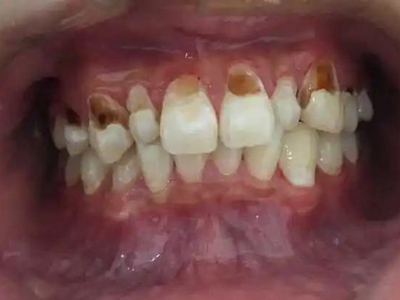

酸蚀症牙齿缺损严重有黄斑图

酸蚀症严重时可导致牙齿发生大块缺损,上门牙侧面有较大空洞,形似虫蛀,缺损处颜色明显发黄,呈黄褐色至深褐色,需积极进行牙齿修复治疗。